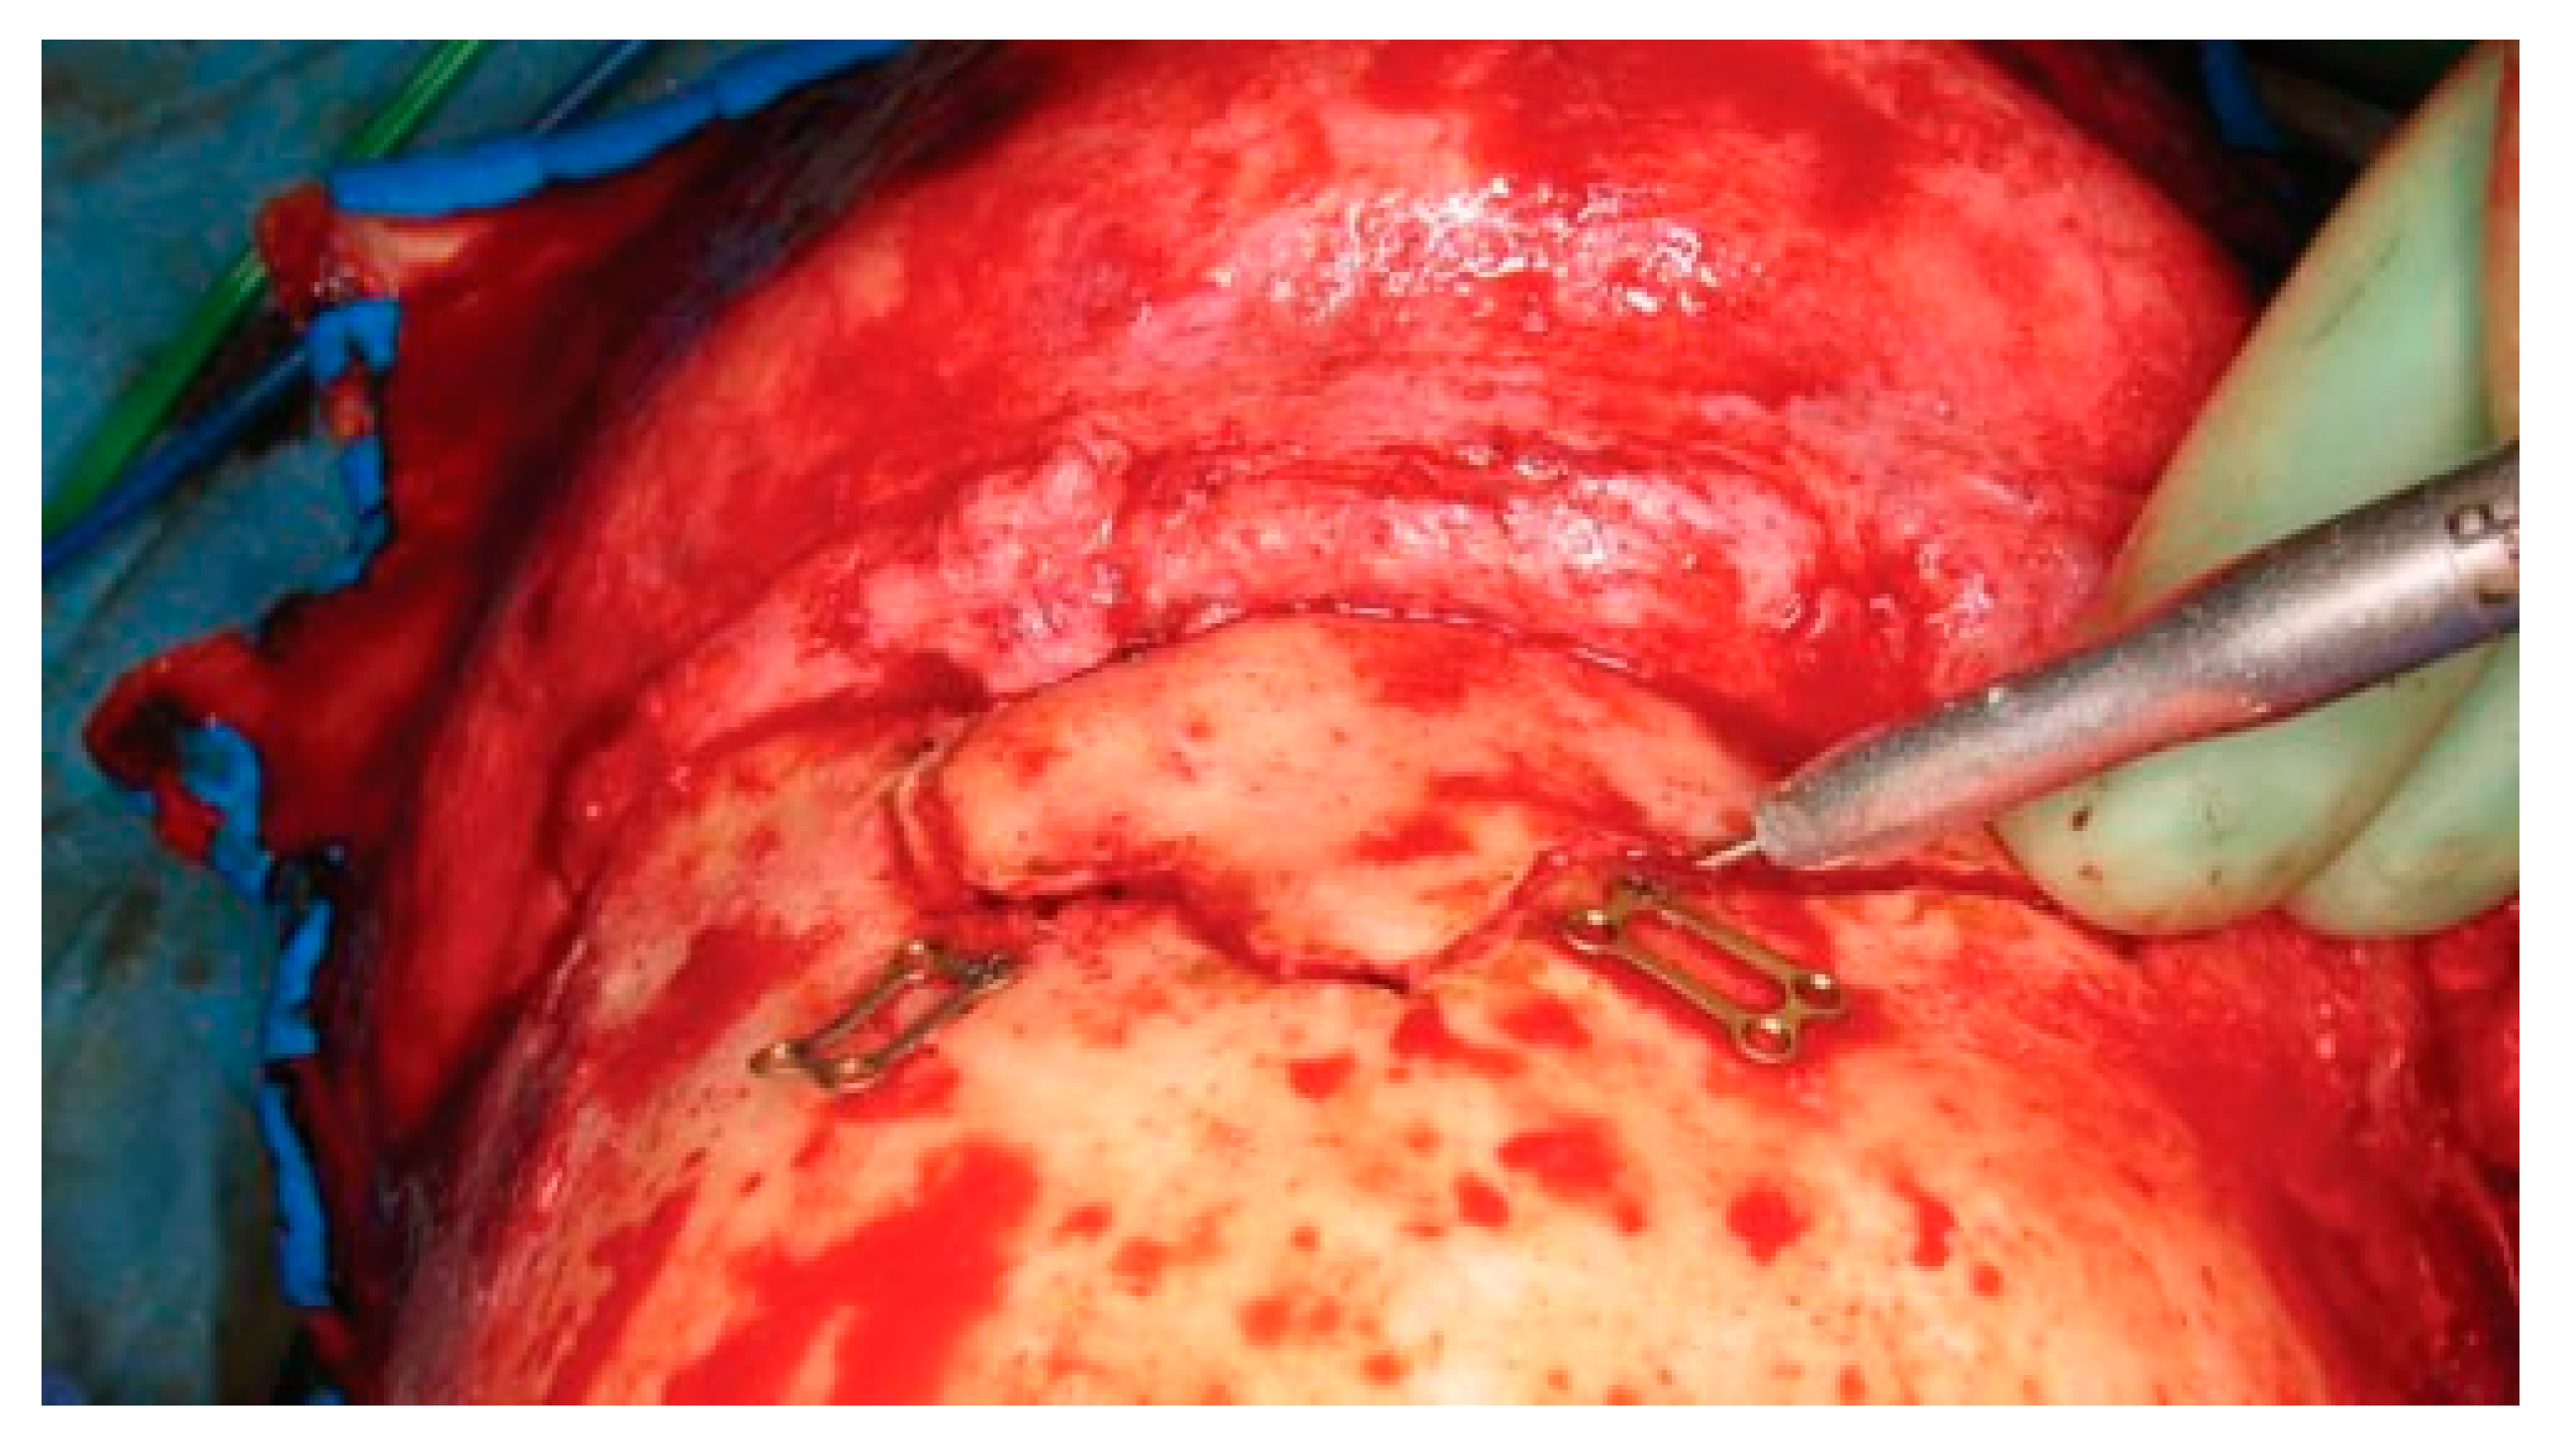

The patient gives consent after being informed of the risks of bleeding, infection, paresthesia, brain injury, CSF leak, meningitis, diplopia, visual loss, external deformity, and late mucocele formation. A coronal flap is used to expose the fracture as previously described. The full pericranial flap should be maintained to repair any CSF leak, dural defect, or obliteration of the sinus. After complete exposure, all anterior table bone frag- ments should be removed and kept moist. Placing the fragments atop a drawing of the fracture will help maintain the anatomic orientation of each segment prior to the repair. With fractures isolated to one side of the sinus, it is often necessary to perform a frontal sinus- otomy to remove the remainder of the anterior table bone. Localization of the sinusotomy cuts can be per- formed in several ways. Historically a ‘‘6-foot penny Caldwell’’ X-ray was used (i.e., anterior-posterior Cald- well X-ray with the patient placed 6 feet from the X-ray tube). However, current digital radiograph technology has made these images difficult to obtain. Intraoperative navigation is accurate but requires a specialized scan and navigation hardware. Alternatively, one tine of a bipolar cautery can be placed on each side of the anterior table. The internal tine is then used to ‘‘walk’’ around the periphery of the sinus, and the outer tine is used to mark an outline of the sinus using a bovie electrocautery (Figure 19). A final technique involves insertion of a light source into the sinus through a fracture line; this trans- illuminates the periphery of the sinus and guides the osteotomy.

Figure 19.

Intraoperative photo demonstrating the use of bayonet forceps to outline the periphery of the frontal sinus.